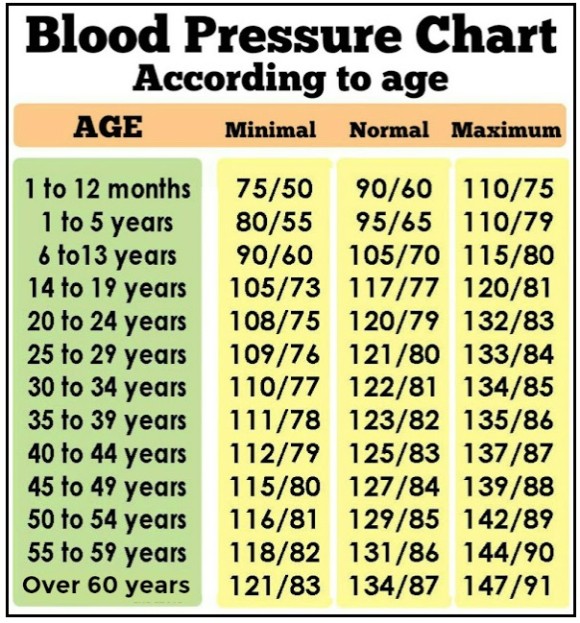

참고로 평균 혈압은

나이에 따라 조금씩 차이는 있지만 보통은 자기 나이+90세면 된다고 한다.

그러나 이것도 동서가 조금은 그 기준이 다르고, 또 나이가 많아짐에 따라 +80 정도로 계산하기도 한다.

만약 30세였다면 30+90=120이 최고혈압대의 정상치이고(혈압은 최고혈압-최저혈압으로 나뉘는데. 최저 혈압 생략)

40살이면 120~130정도가 평균이고

50세라면 130140 정도가 평균이다.

혈압은 나이가 들수록 자연스럽게 올라가게 돼 있다.나이가 들수록 위험해.자기 나이 평균 혈압보다 높은 혈압을 가지고 있다면 고혈압

(혈압의 단위는 mmHg = 밀리미터 에지)

연령에 따른 혈압 수치

과거에는 나이와 상관없이 일률적으로 정상 혈압의 범위를 참고했지만 나이가 들수록 자연스럽게 오르는 혈압 상승분을 인정하는 분위기라던데.결정은 본인이 해야 한다.

또 혈압 수치를 무조건 믿어서도 안 된다.겨울에 혈압이 더 올라가고, 하루라도 밤과 낮 시간대의 혈압이 다르기 때문이며,

혈압측정 방식의 차이와 혈압측정기의 기계적인 차이도 존재하므로 절대 신뢰해서는 안 된다는 것.

심리적인 이유로 혈압의 차이가 발생한다고도 한다.